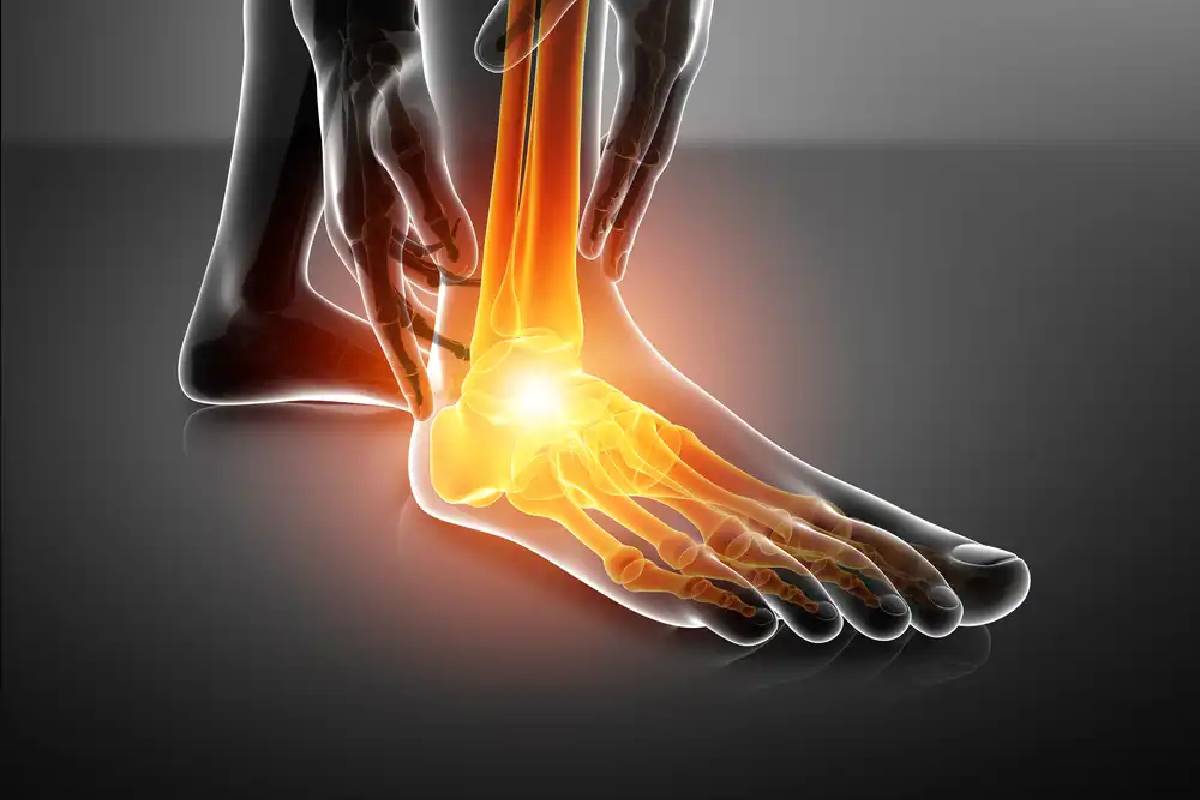

2. سندروم سینوس تارسی

این سندروم که با التهاب در کانال بین پاشنه و استخوان مچ پا همراه است، اغلب در افراد با کف پای صاف یا کسانی که فعالیتهای سنگین انجام میدهند، دیده میشود. درد آن معمولاً در قسمت خارجی مچ پا احساس میشود و میتواند با بیثباتی همراه باشد.

برای تشخیص دقیق علت درد روی پا، پزشک ابتدا معاینه فیزیکی انجام میدهد و به دنبال علائم مانند تورم یا حساسیت میگردد. تصویربرداری مانند اشعه ایکس برای بررسی شکستگیها مفید است. در موارد پیچیده، ام آر آی یا سی تی اسکن برای دیدن بافتهای نرم استفاده میشود. آزمایش خون میتواند عفونت یا بیماریهایی مانند نقرس را شناسایی کند. گاهی نوار عصب و عضله یا بیوپسی لازم است تا علت دقیق مشخص شود.